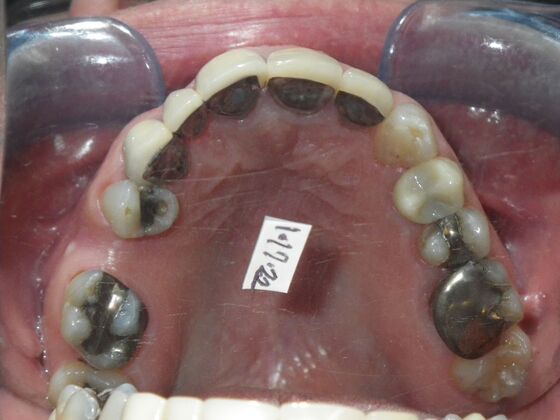

Cosmetic Changes with Veneers and Crown and Bridge: Case 5

Patient wanted to see about getting his upper front crowns replaced. He has had them for 35 plus years. Also concerns about his gums receding and the metal margins of crowns showing. Also talked with him about the need for crown lengthening which would have helped decrease the gummy smile; however, he chose not to do this. I thought just replacing the existing crowns to the existing gingival margins would be a great help. So the existing porcelain/metal crowns were removed and new all ceramic single unit crowns placed from upper right cuspid,lateral incisor and right central incisor. Then a 3-unit all ceramic bridge was placed from upper left central incisor to upper left cuspid. This patient and most of all his wife were very pleased with the end result.